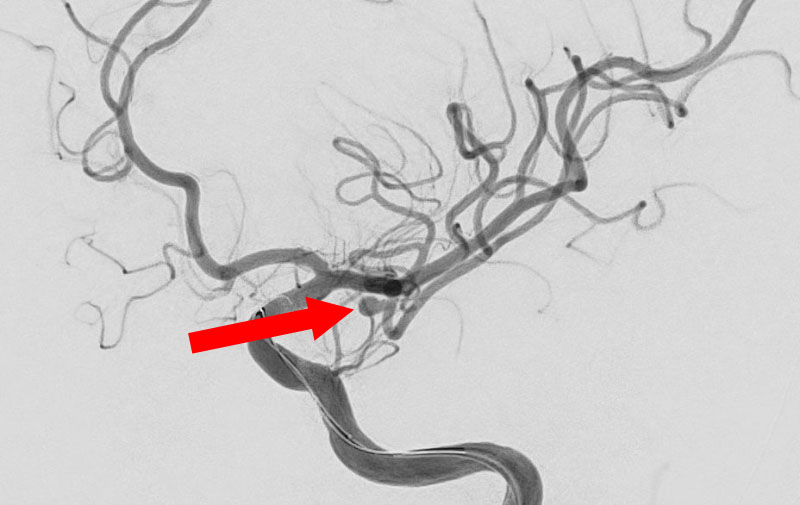

'25年11月

くも膜下出血

右内頚動脈後交通動脈

分岐部動脈瘤破裂

60代

救急外来

No.1593 手術後